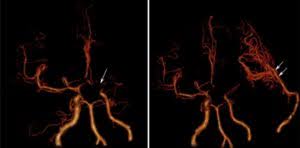

3D Vascular Imaging

3D vascular imaging of the brain showing successful revascularization surgery for moyamoya disease with extracranial-to-intracranial bypass.